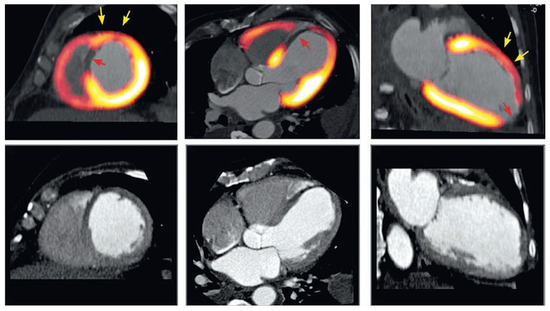

Coronary CT angiography (CTA) is emerging as a highly effective alternative imaging technique for the assessment of coronary artery disease (CAD). The rapid evolution of multidetector CT scanners has lead to major improvement in temporal resolution o...